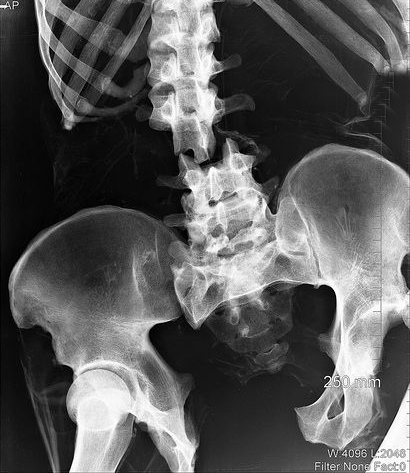

Чтобы точно диагностировать перелом позвоночника необходимо немедленно обратится к специалистам, которые с помощью рентгена лил МРТ смогут поставить точный диагноз.

Особое внимание следует уделить компрессионному перелому позвоночника. Это очень серьезное повреждение, которое может привести к серьёзным повреждениям спинного мозга. Компрессионный перелом происходит в результате сжатия тела позвоночника. Такая травма чаще всего происходит вследствие неправильного падения на ноги, ягодицы, а также во время внезапного сгибания туловища во время выполнения спортивных упражнений.